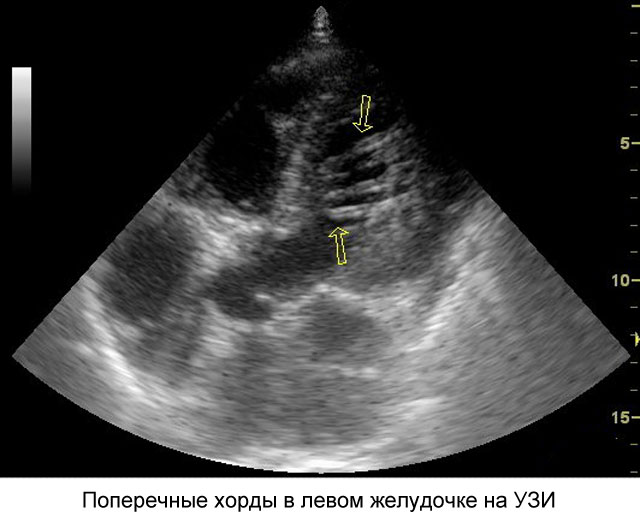

Основным способом диагностики данной аномалии является эхокардиография (Эхо КГ) – ультразвуковое исследование сердца. Дополнительное обследование с использованием допплеровского сканирования помогает определить расположение, толщину и длину аномальной нити, а также место ее прикрепления и оценить скорость кровотока в этой области.

В данной статье мы подробно рассмотрим такую небольшую аномалию сердца, как дополнительная хорда левого желудочка. Чаще всего она выявляется у детей до 18 лет, однако некоторые люди могут жить с этим диагнозом многие годы, не испытывая никаких изменений в работе сердца. Обычно дополнительная хорда обнаруживается случайно, во время обследования по поводу другого заболевания или в ходе профилактического осмотра. При прослушивании сердца или на ЭКГ она не определяется, и точный диагноз можно установить только после проведения эхокардиографии. Если врач слышит шум в сердце, он может заподозрить наличие этой аномалии и порекомендовать пройти ультразвуковое исследование для подтверждения или опровержения диагноза.